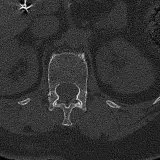

PACSで期待されるツールを完備した完全インタラクティブな症例 — スクロール、ウィンドウ調整、ズーム、パン、計測、ROI、フルスクリーンモード。

重要な所見を症例画像上に直接ハイライトする豊富なアノテーション。症例解説内のリンクされた所見をクリックすると、スキャン上の正確な位置へジャンプできます。

アノテーション付きの画像所見とイラストで効率的に学習